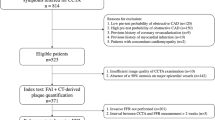

Patients who underwent both CCTA and FFRICA measurement within 2 weeks were retrospectively included. ML-based FFRCT, volume of subtended myocardium (Vsub), percentage of subtended myocardium volume versus total myocardium volume (Vratio), high-risk plaque features, minimal lumen diameter (MLD), and minimal lumen area (MLA) along with other parameters were recorded. Lesions with FFRICA ≤ 0.8 were considered to be functionally significant.